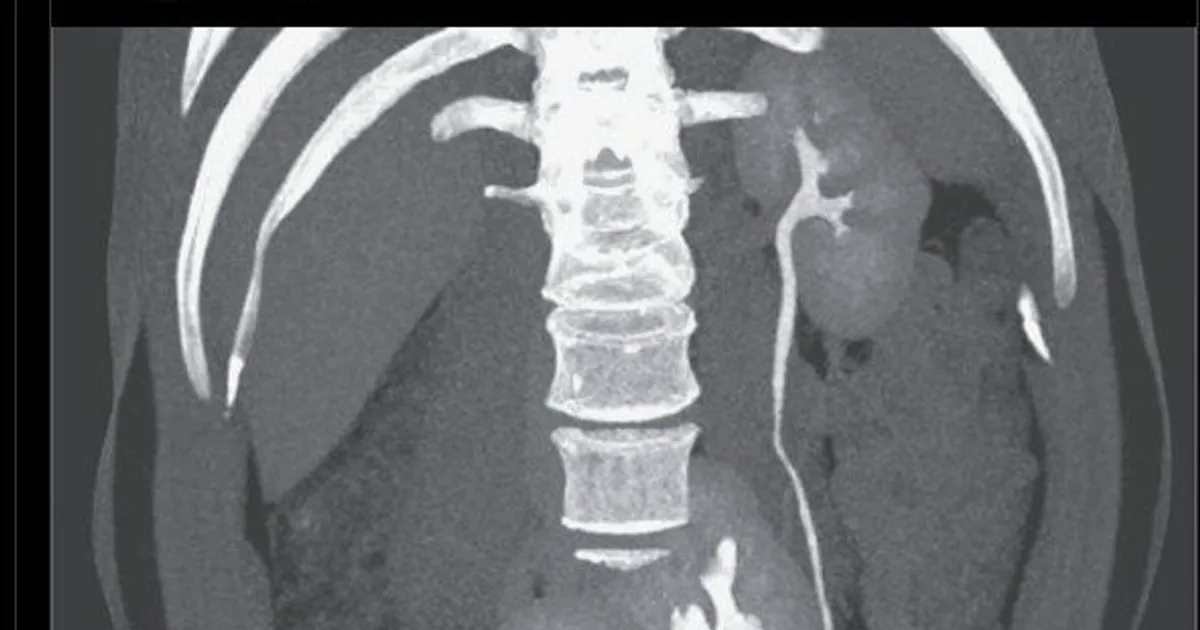

의사: “당신은 생물학적 복권에 당첨됐군요.” 환자: “무슨 말씀이세요?”

AI인가? 싶어 좀 찾아보니 저널에 있는 자료네요

https://www.nejm.org/doi/full/10.1056/NEJMicm1910376